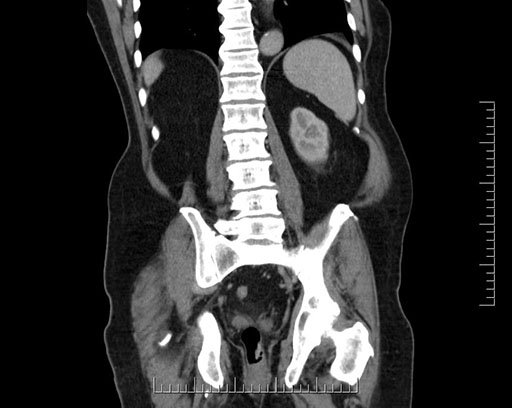

Whipple (pancreaticoduodenectomy) [case 7]

Imaging Analysis

Look through the patient's CT scan to identify any areas of concern for the necessary procedure.

Coronal - stented